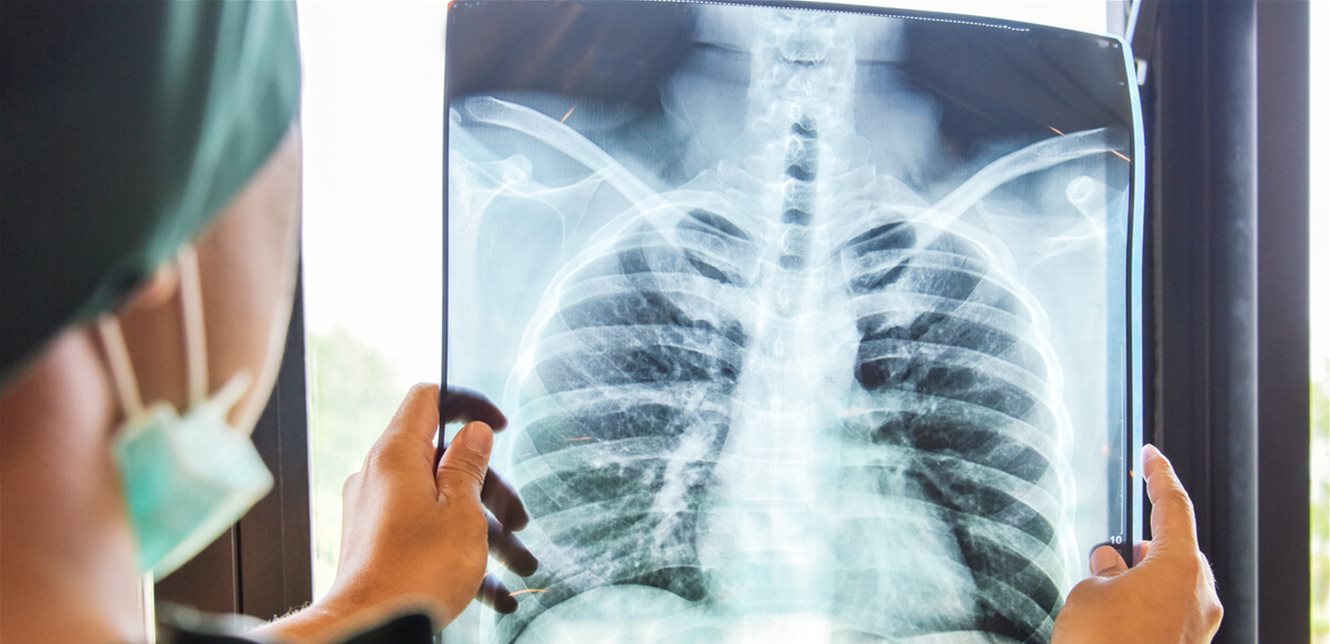

أما التشخيص، فيتم عادة عبر إجراء صورة شعاعية للصدر، إضافة إلى تحليل عينة من البلغم للكشف عن البكتيريا المسببة للمرض. ويؤكد رضوان أن الكشف المبكر يلعب دورًا أساسيًا في الحد من انتشار العدوى وحماية المجتمع.